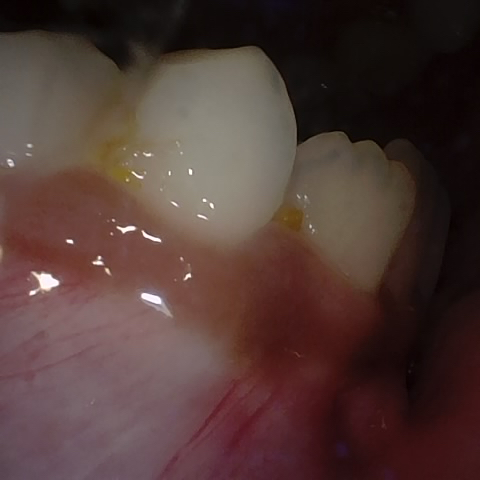

Annotated as "Good"